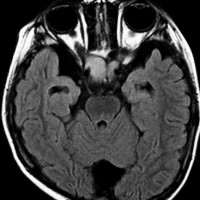

幼児の視路の毛様粘液性星細胞腫です。T2強調画像(左側)で白く高信号に写るのが特徴です。ガドリニウム増強ではまだらになっていますが,均一に真っ白に高信号になることも多いです。乳幼児のものは,ドロドロに柔らかい腫瘍です。

生後7カ月の幼児です。目が揺れるようになり(振り子様眼振)眼科を受診して腫瘍が発見されました。小児脳腫瘍の治療ができる病院へと紹介されました。

1ヶ月後にまたMRI検査がされました。乳児ですから検査にも麻酔が必要です。腫瘍は明らかに大きくなっています。左視神経から視索の腫瘍化が著しいので右側だけかすかに視力が残っているかもしれません。視力は明かりがわかる程度(明暗弁)と評価されました。